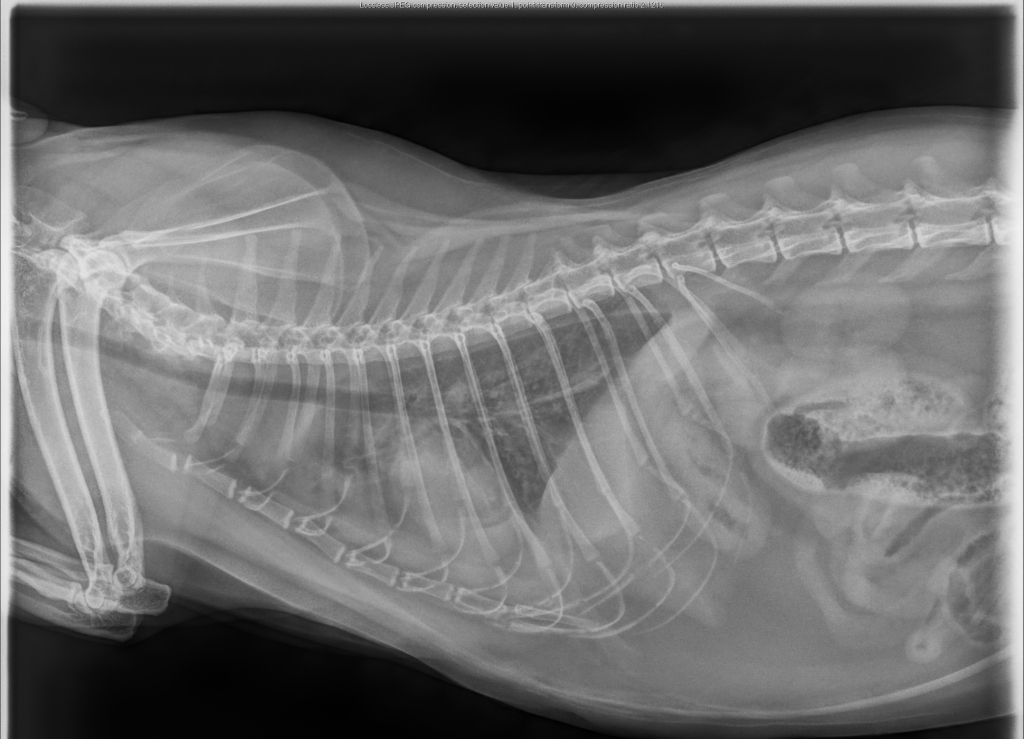

RADIOLOGY

STAT Consults On Time

Radiology Services